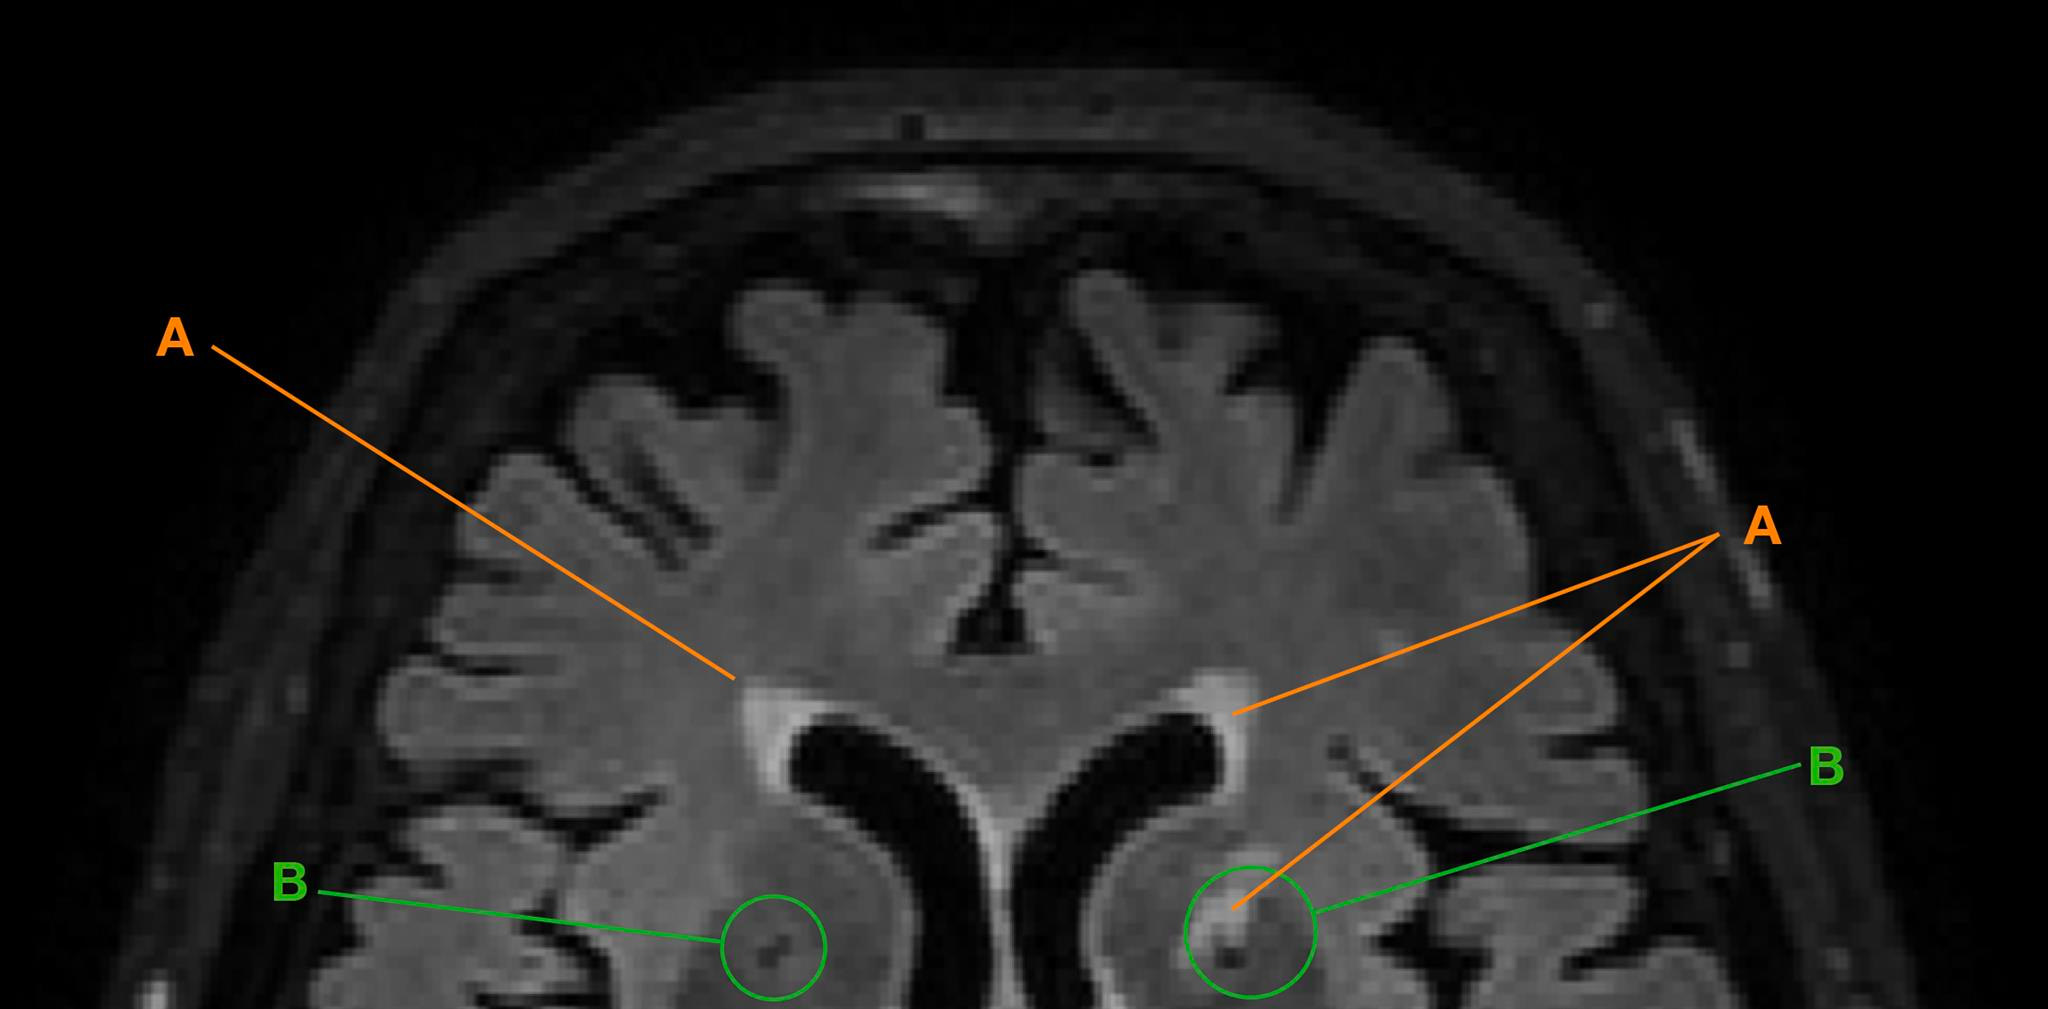

Die Erstautorin Isabel Hotz vermass im Rahmen ihrer Doktorarbeit mit teilweise neuen, automati-sierten Methoden sogenannte Lakunen und Hyperintensitäten der weissen Hirnsubstanz. Diese Degenerationsprozesse zeigten sich als «weisse Flecken» oder «schwarze Löcher» auf den digi-talen Aufnahmen. Die Ursachen dafür sind nicht eindeutig bekannt und können in kleinen, nicht bemerkten Hirn-infarkten, einer geringeren Durchblutung oder im Abbau von Nervenbahnen und -zellen liegen. In der Folge können Einschränkungen kognitiver Leistungen auftreten, vor allem dann, wenn dieser Zerfall an strategisch wichtigen Stellen des Gehirns auftritt.